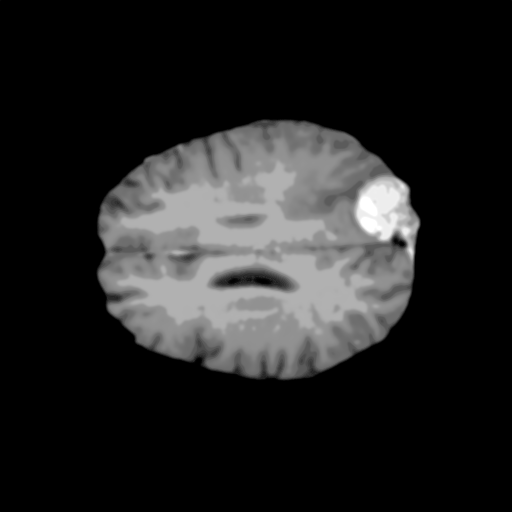

Extensive experiments have been performed in the current setup, and experimental outcomes are reported with the demonstration of numerical and statistical analyses using the proposed QFS-Net, QIS-Net [39], convolutional U-Net [18] and Residual U-Net (URes-Net) architectures [20]. The human expert segmented skull-tripped contrast enhanced DSC brain MR input image slices of size and ROIs are provided in Figure 5 as samples. The demonstration of QFS-Net segmented images followed by the essential post-processed outcome on the slice no. for class level with four distinct activation schemes () are shown in Figure 6. It is evident from the experimental data provided in Table LABEL:tab1 that the proposed QFS-Net performs optimally for the -connected quantum fuzzy pixel information heterogeneity assisted activation () with and gray scale set in comparison with other thresholding schemes and gray scale sets under the four evaluation parameters () [44]. The segmented tumors obtained using the proposed self-supervised procedure under class transition levels with four different thresholding schemes , , and are demonstrated in Figures 7- 8 for the class boundary sets and [39], respectively. The segmented images using the remaining two class boundary sets ( and ) [39] are provided in the supplementary materials section. The segmented ROIs describing the whole tumor region after the masking procedure using QIS-Net, U-Net and URes-Net are also reported in Figure 9.